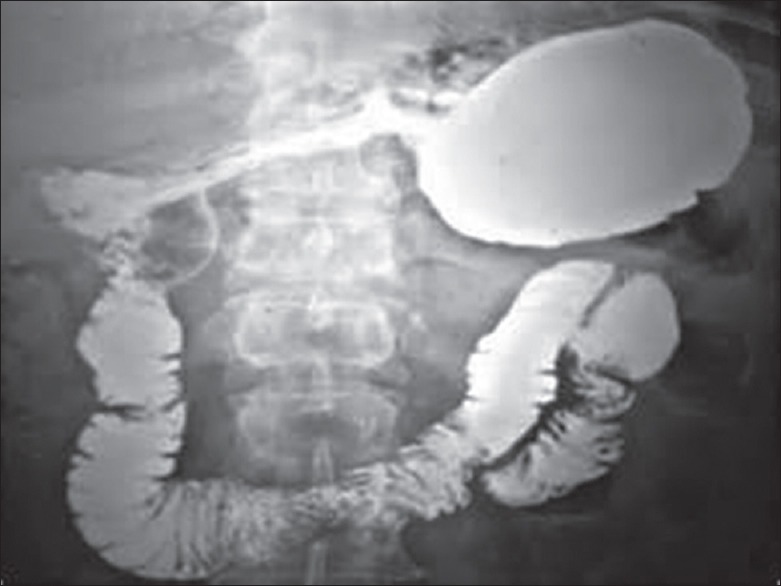

胃扭转在临床表现、诊断、影像学支持、病理行为和评价等方面具有不同的意义,是一种罕见的医学实体,对诊断和治疗的怀疑指数要求很高。当急性出现时,很容易被发现。然而,在亚急性表现的患者中,由于发作性扭转和解扭转,症状模糊。如果在症状期进行影像学检查,可以建立明确的术前诊断。本报告的主要目的是强调有必要对这种疾病保持高度的怀疑指数,并在症状期间对患者进行成像。

Gastric volvulus is a rare medical entity that requires high index of suspicion for diagnosis and treatment as it has different implications in terms of clinical presentation, diagnosis, imaging support, pathological behavior, and evaluation. When it presents acutely, it may be easily detected. However, in patients with subacute presentation, symptoms are vague due to episodic twisting and untwisting. Definite preoperative diagnosis can be established if imaging is performed during symptomatic interval. The main aim of this report was to stress on the need for keeping high index of suspicion for this medical condition and for imaging the patient during symptomatic interval.